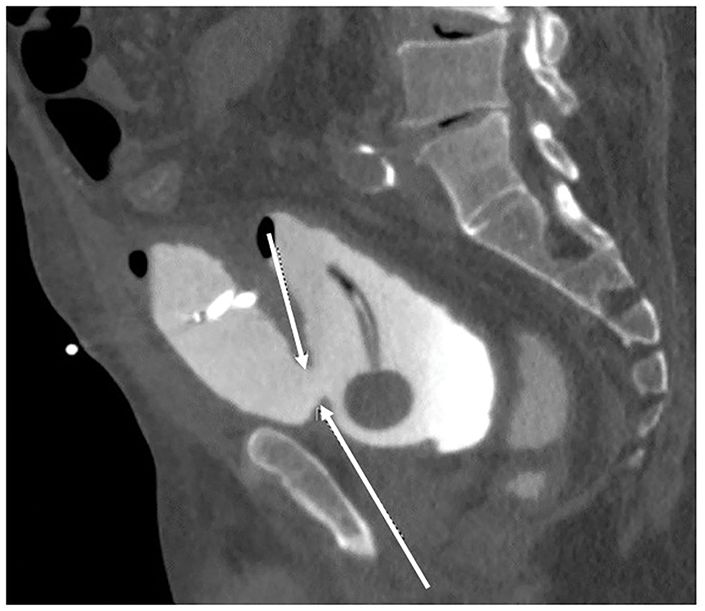

About 48 h after cystoscopy, he developed lower abdominal pain, anuria, and a slight rise in creatinine level to 1.06 mg/dL from 0.84 mg/dL. A CT cystogram was obtained, demonstrating a 2 × 2 cm extraperitoneal anterior bladder wall perforation with extravasation of contrast to the space of Retzius (Figure 2).

FIGURE 2. Extraperitoneal extravasation of contrast into the space of Retzius was demonstrated on computerized tomography (CT) cystogram after spontaneous rupture of the urinary bladder. Arrows show the defect at the anterior bladder wall